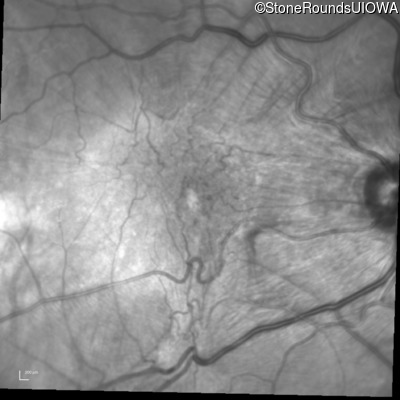

Fundus Montage - Right - 10/125

Exemplar